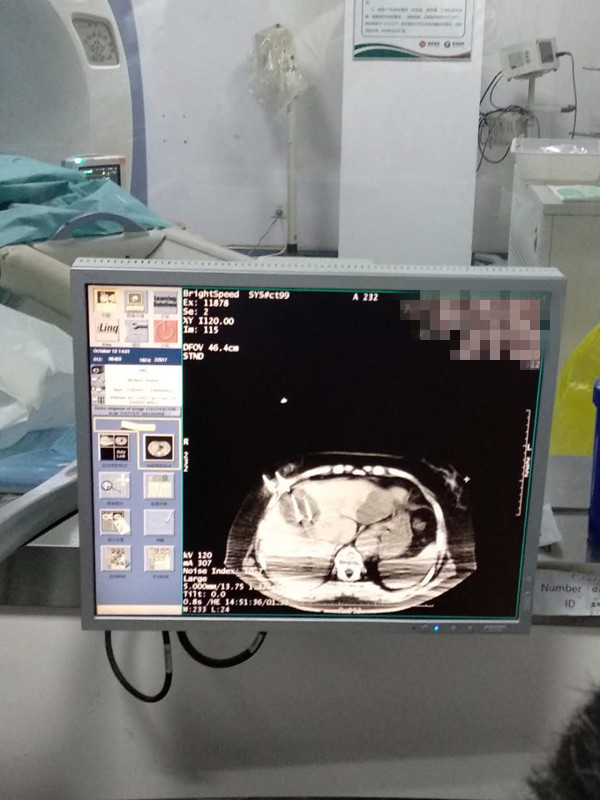

73岁患者肝部氩氦刀冷冻消融